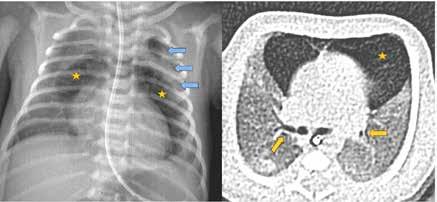

Debido al empeoramiento clínico se solicitó una ecografía de abdomen durante la cual estuvo presente el equipo tratante y en la que se evidenció aumento del líquido libre de aspecto ecogénico sin otras alteraciones. Sin embargo, ante la evolución tórpida y la localización de la contusión abdo minal se comunicó al radiólogo la posibilidad de una perforación intestinal, quien realizó una segunda exploración ecográfica enfocada en las zonas cefálicas y anteriores del abdomen en las que se ubicaría el aire, entonces se visualizaron artefactos en la superficie hepática que sugerían burbujas aéreasextraluminales (Figura 2A). Se realizó una radiografía toracoabdomi nal (RxTA) que confirmó la presencia de neumoperitoneo subdiafragmático bilateral (Figura 2B).

Figura 2. Ecografía con burbujas aéreas extraluminales en la superficie hepática sugestivas de neumoperitoneo (A, flechas). RxTA con neumoperitoneo subdiafragmático bilateral (B, flechas).

Figura 2. (Izq.) radiografía de tórax en proyección AP a las 36 horas de vida donde se objetiva neumotórax de nueva aparición (flechas azules) y una zona de hiperclaridad alrededor de la silueta cardíaca que sugiere importante neumomediastino (estrellas amarillas). (Der.) TC de tórax sin contraste intravenoso en ventana de pulmón que confirma la presencia de neumomediastino (estrella amarilla). Se objetivan focos de consolidación periféricos y bandas lineales de densidad aire paralelas y adyacentes a las vainas broncovasculares (flechas amarillas).